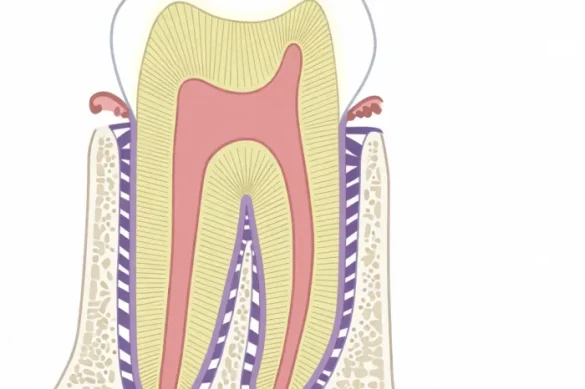

The alveolar bone, additionally called the alveolar manner or alveolar ridge, is the part of the jaw bones in human beings that includes the enamel sockets. These sockets, termed dental alveoli, are in which tooth are anchored. The alveolar bone is included via way of means of gum tissue in the mouth and is an vital a part of each the maxilla (higher jaw) and the mandible (decrease jaw).

Alveolar bone is classed as a form of cortical and trabecular bone. This approach it includes compact bone (cortical bone) and spongy bone (trabecular or cancellous bone). The compact bone bureaucracy the outer layer, supplying power and stability, whilst the trabecular bone lies within, contributing to resilience and flexibility. More specifically, alveolar bone is a specialised form of bone tailored to aid and reply to the mechanical forces generated via way of means of tooth for the duration of chewing and biting.

The cortical bone, or compact bone, bureaucracy the facial and lingual plates surrounding the alveolar bone. These plates are commonly approximately 1.five to a few mm thick over the posterior tooth. The cortical bone presents structural power and durability. It is vital as it resists the outward stress from the tooth and enables preserve the form of the jaw.

Inside the alveolar bone, there may be a layer of trabecular or cancellous bone. This form of bone is much less dense than cortical bone and includes many areas or pores. The trabecular bone acts like a surprise absorber, assisting to hose down the forces from chewing and biting. Between the alveolar bone right and cortical plates lies the trabecular bone, assisting the tooth and facilitating flexibility.

The alveolar bone right is the a part of alveolar bone that immediately traces the enamel socket. It is comprised specially of compact bone and is likewise called the package bone. It immediately interfaces with the periodontal ligament, which anchors the enamel roots.

The alveolar bone includes numerous wonderful parts:

- Alveolar Crest: The alveolar crest paperwork the cervical rim of the bone close to the necks of the tooth. In healthful individuals, it lies barely apical (below) the cementoenamel junction (CEJ), normally through approximately 1.5–2 mm.

- Interdental Septum: The bone located among adjoining tooth is known as the interdental septum. It affords assist for the tooth and keeps spacing.

- Lamina Dura: On radiographs, the location adjoining to the periodontal ligament seems because the lamina dura. This is an vital medical landmark.

The alveolar bone is penetrated through nerves, blood vessels, and lymphatics, making sure the deliver of vitamins and elimination of waste.

Sharpey fibers, a part of the periodontal ligament, are inserted into the alveolar bone proper. These fibers assist anchor the tooth firmly inside the sockets and transmit mechanical forces from the tooth to the bone.